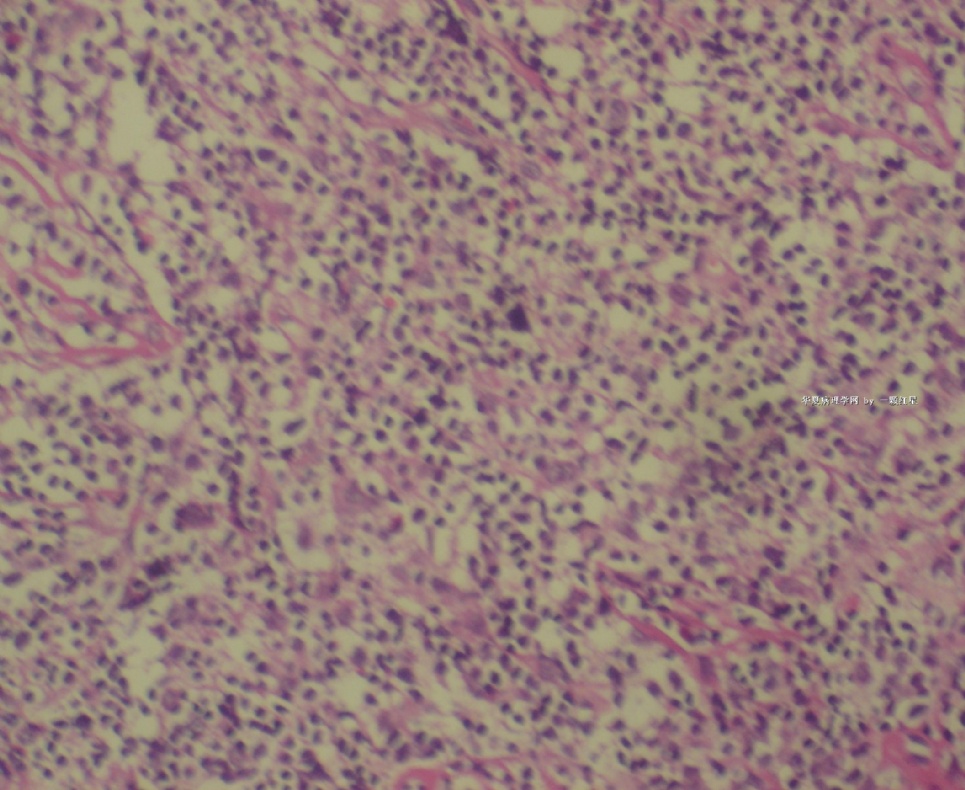

标本名称:  左前臂数个大小不等的皮下肿物。

• 左前臂数个大小不等的皮下肿物     淋巴瘤?图2

图2

病例不错。细胞胞浆透亮,间质血管丰富,图片不是很清晰,似乎有嗜酸粒细胞?

恶性,首先考虑T-NHL。IHC证实。

既往有NHL病史,图片不太清晰,细胞弥漫,胞浆透亮,首先考虑T细胞淋巴瘤。